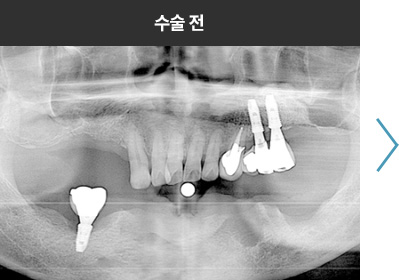

BMP를 이용한 수술 사례      I

치료 기간 : 2023.03.22 ~ 2023.09.15

* 상기 사례의 경우, 해당 의료기관에서 진료를 한 환자분의 동의를 얻어 사용되었습니다. * 치료 전후의 사진은 동일 인물과 동일한 조건에서 촬영 되었음을 알려드립니다.

* 모든 수술 및 시술은 개인에 따라 부작용고지 : 임플란트치료는 치료 후 감염,

염증, 연조직합병증, 출혈, 감각이상 등의 부작용이 있을 수 있습니다.

의료진과 충분히 상의 후 신중하게 결정하시기를 바라겠습니다.